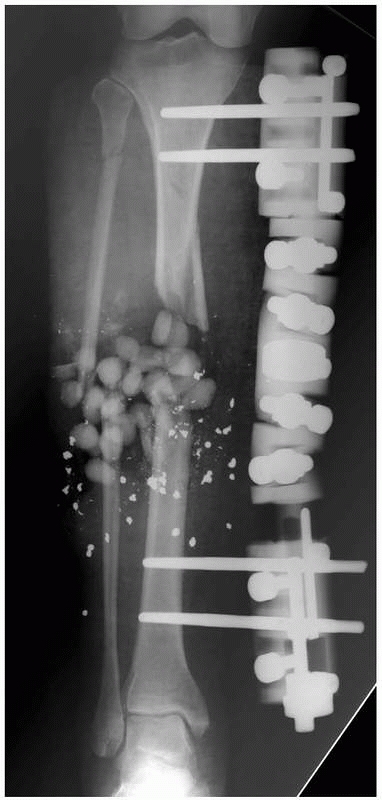

FIGURE 8-33 A. Severe bone and soft tissue loss stabilized with a ring fixator. B. Gradual distraction (compression) across defect gradually closes down the defect via soft tissue transport. (continues)

|

![]() |

FIGURE 8-33 (continued) C. Skin grafting was performed over reconstructed soft tissues, once docking of the bone ends had been completed. D. Healed tibia later underwent limb lengthening.